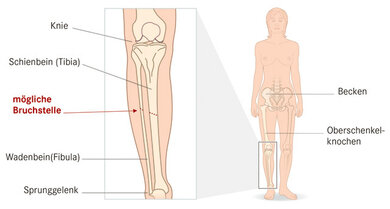

Unterschenkelbruch (Unterschenkelschaftfraktur)

© W&B/Jörg Neisel

Der Unterschenkel besteht aus zwei Knochen. Dem Schienbein und dem Wadenbein (siehe Skizze). Zum Körperstamm hin bildet das Schienbein einen Teil des Kniegelenkes, fußwärts gerichtet bilden Schien- und Wadenbein das obere Sprunggelenk. Bei einem Unterschenkelbruch können die Knochen im mittleren Bereich gebrochen sind (Unterschenkelschaftfraktur), aber auch im Bereich der angrenzenden Gelenke. Ist dies im Bereich des oberen Sprunggelenkes spricht man auch von einer oberen Sprunggelenksfraktur (OSG-Fraktur).

Betrifft der Bruch den mittleren Bereich (Schaftbereich der Knochen) sind häufig beide Knochen gebrochen. Es kann aber auch jeweils nur einer der beiden Knochen einzeln gebrochen sein. Aufgrund der Lage und Dicke handelt es sich dabei deutlich häufiger um das Wadenbein. Dann ist von einem Bruch des Wadenbeins (Fibulafraktur) oder des Schienbeins (Tibiafraktur) die Rede.